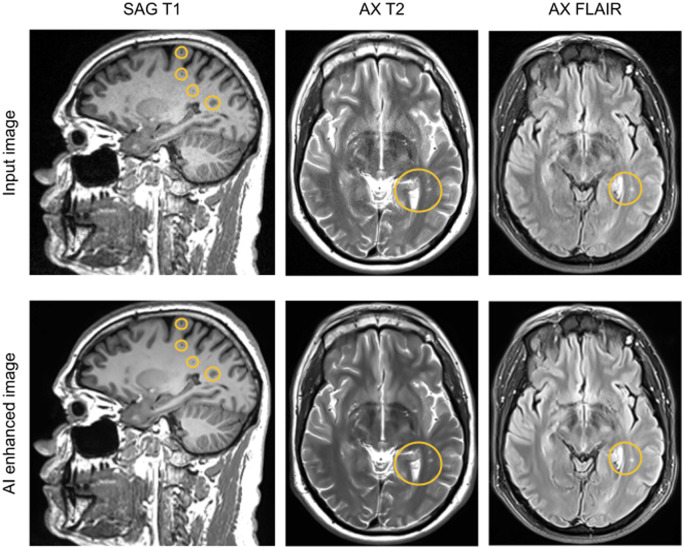

Purpose: To evaluate a vendor-agnostic AI-based approach to remove image degradation artifacts in highly accelerated MRI scans, improving image quality and reducing scan time.

Results: Images from 101 adults from 5 sites and 6 scanner models from different vendors were enrolled. 89% of imaged subjects had noteworthy imaging features or pathology. Model outputs were rated superior to model inputs (P < .001) and most were either non-inferior (P inf  > .05) or superior (P sup  < .05) to baseline images in qualitative metrics of image quality and feature visibility. Quantitative evaluation of signal-to-noise ratio and contrast-to-noise ratio improved for model outputs compared to inputs (P < .001) or baseline images (P < .005). Apparent resolution measured using the full width at half maximum or minimum was either enhanced (P sup  < .05) or preserved (non-superior P sup  > .05 and non-inferior P inf  > .05). The scan time was reduced by an average of 29% (19%-41% per sequence).

Conclusion: This vendor-agnostic AI-based method achieved robust scan time savings without loss of image quality, potentially allowing for reduced cost and improved patient experience.